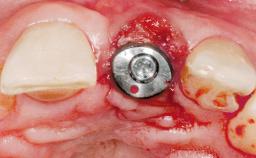

A 30-year-old female patient had lost tooth 21 and was referred to our clinic for consultation and treatment. Due to advanced apical infection, tooth 21 had been extracted two months earlier at another clinic and an acrylic-resin tooth had been bonded to the adjacent teeth. The patient desired implant treatment to avoid any damage to the adjacent natural teeth. While the patient had no history of any systemic disorder, she was a heavy smoker and exhibited medium to advanced periodontitis in the entire jaw. After the initial treatment to achieve a pocket probing depth of less than 4 mm and no bleeding on probing, a decrease in the height of the papillae mesial and distal to the extraction site and overall gingival recession were observed.

| Bone Augmentation | Horizontal|Staged |

| Augmentation Materials | Autogenous chips|Membrane |

| Abutment Type | CAD/CAM |